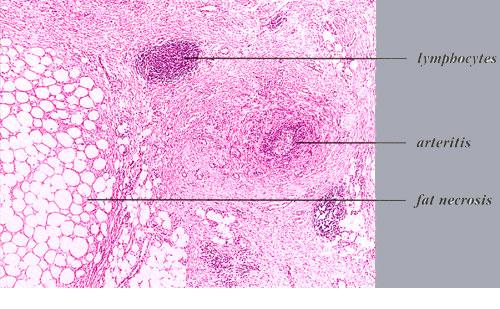

Nodular vasculitis = التهاب الاوعية العقيدي